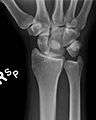

![]() The left lunate bone | |

Bone

The proximal surface of the lunate bone is smooth and convex, articulating with the radius. The lateral surface is flat and narrow, with a crescentic facet for articulation with the scaphoid. The medial surface possesses a smooth and quadrilateral facet for articulation with the triquetral. The palmar surface is rough, as is the dorsal surface. The dorsal surface is broad and rounded. The distal surface of the bone is deep and concave.[3]